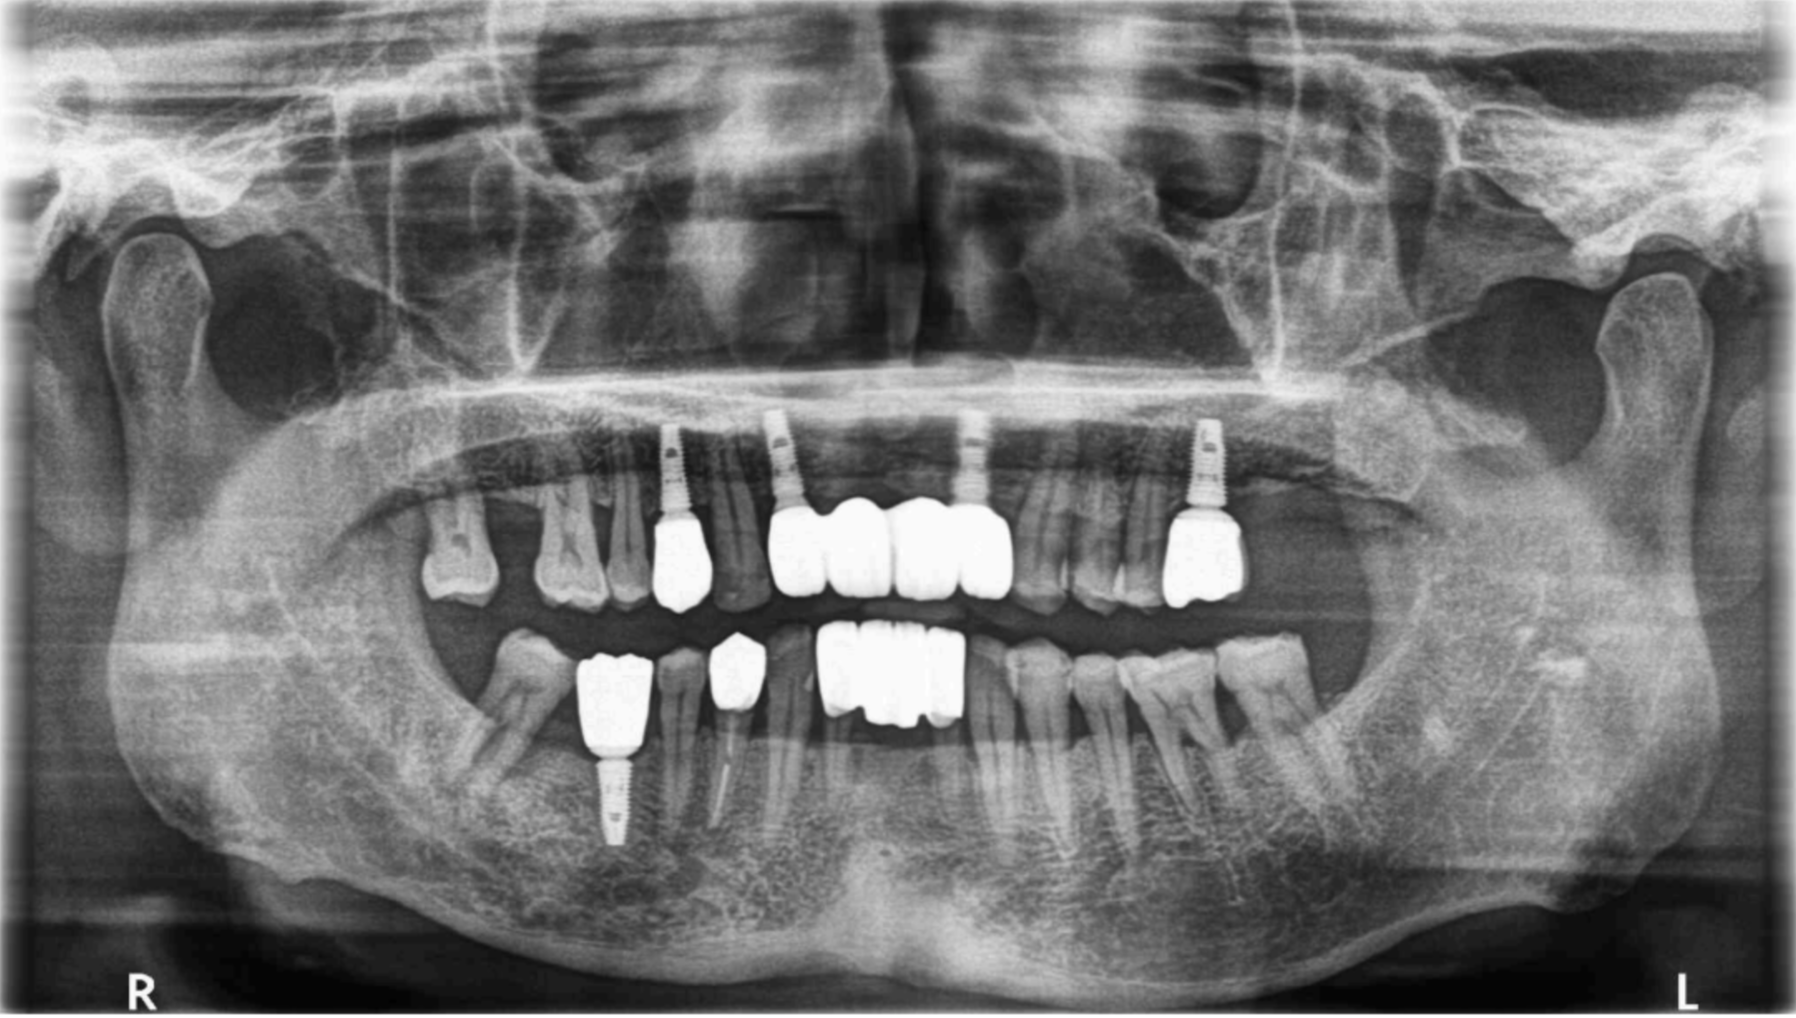

全口重建|不要輕忽缺牙造成的蝴蝶效應:全口磨耗、假牙崩壞案例-黃先生

【全口重建:全口磨耗和缺失後牙支撐】 【治療醫師:林農翔 醫師】 黃先生因為前牙假牙搖動無法進食而走進診間,經過電腦斷層和照相檢查判斷,告訴他現在牙齒會有現在的 …